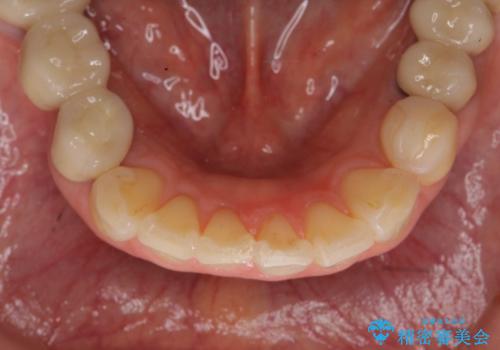

前歯の突き上げを改善する インビザライン による小矯正

- 下顎前歯のガタつきにより上顎前歯のクラウンに突き上げ・動揺が認められ、また歯ぎしりもあることから下顎前歯のみの小矯正をインビザライン で行うこととなりました。

噛み合わせが強くまた下顎に前歯にもガタつきが認められる場合、歯ぎしりやくいしばることで上顎前歯に大きな力がかかり歯の破折やクラウン損傷の大きなリスクとなることがあります。

このおようなリスクを最大限回避するためにも、咬合調整や小矯正により大きな力が上顎前歯にかからないような環境を整えることが大切です。